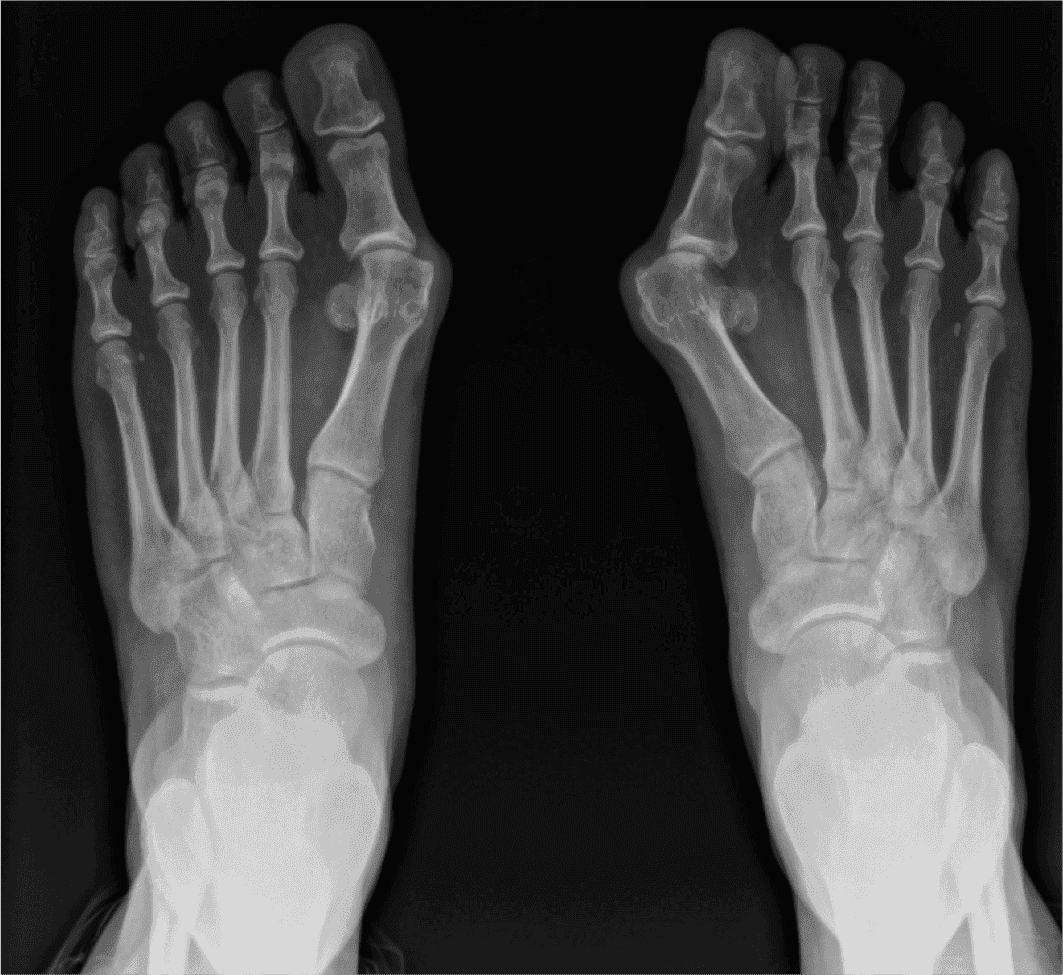

Bunion Surgery Orange County Irvine Southern California